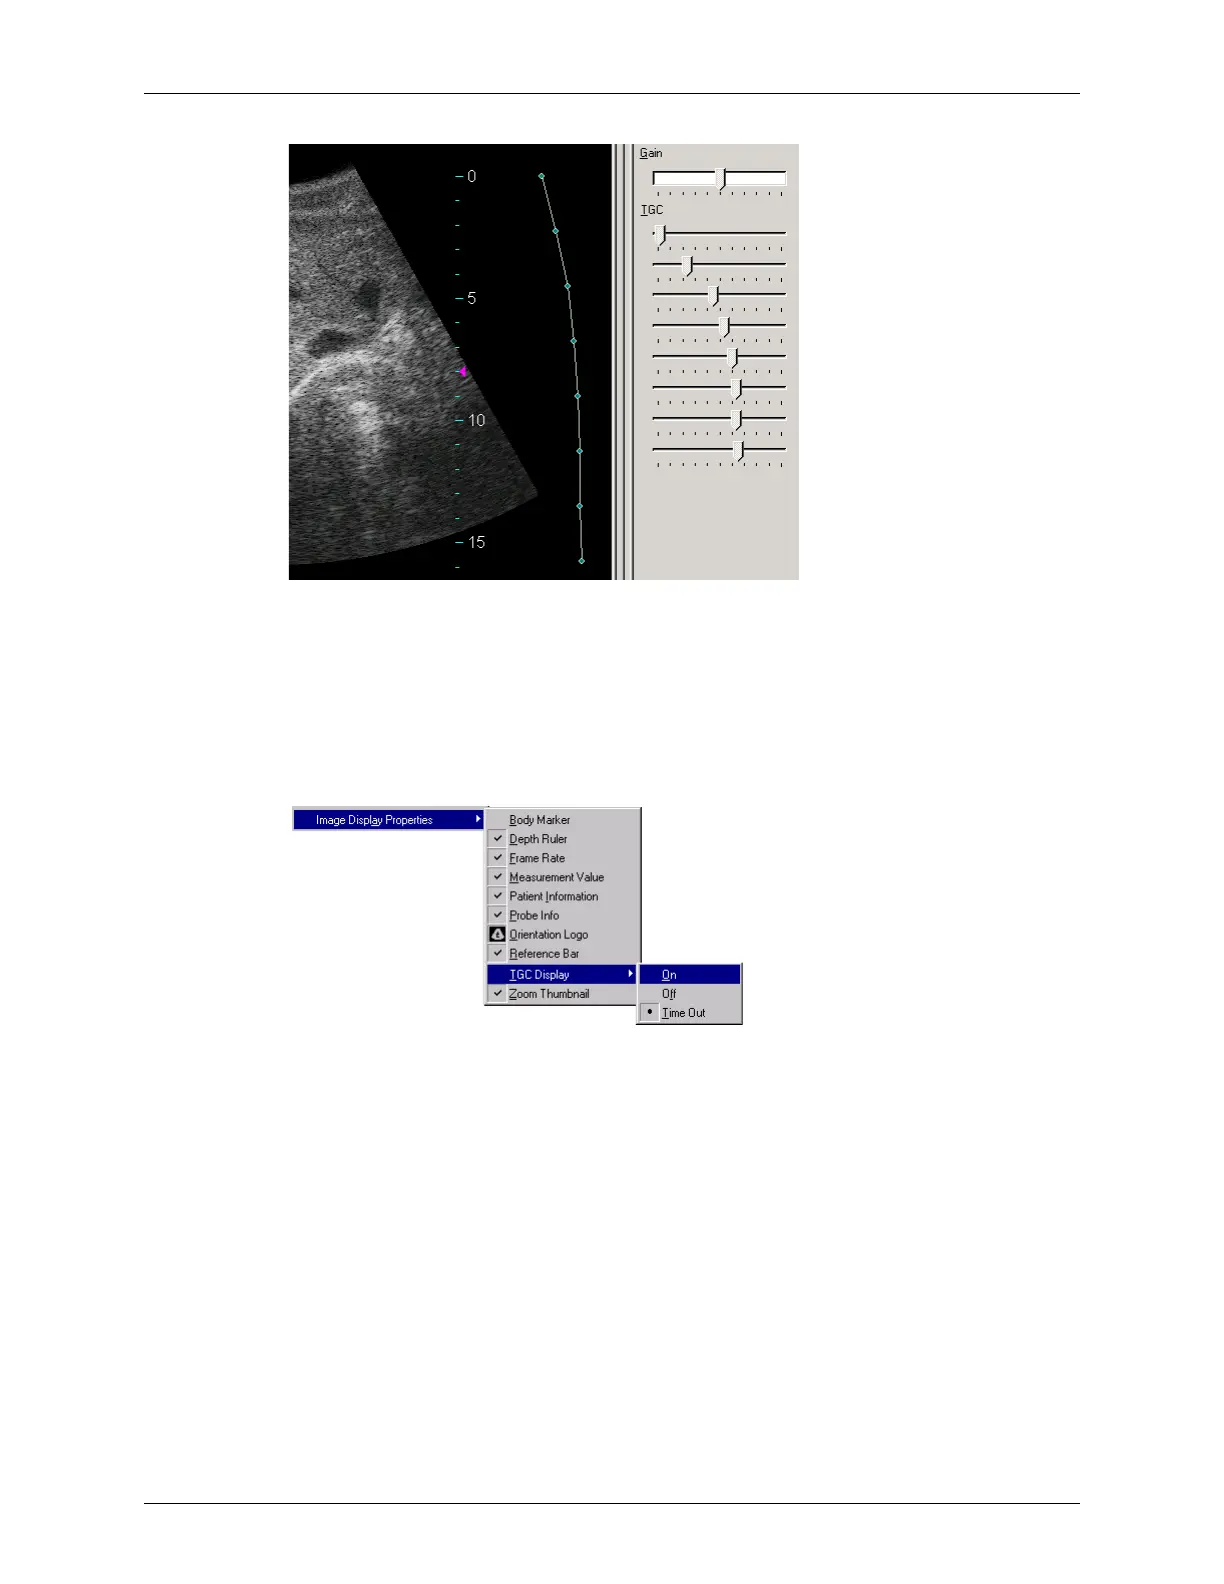

Example TGC Curve on an Image

Each slider controls one dot on the curve. You can adjust the TGC sliders individually as

needed. Drag a slider to the left to decrease the gain, or drag it to the right to increase the

gain. You can also use the keyboard arrow keys; after clicking the 2D tab to select the

Gain control, press the down arrow key to select a TGC slider, then use the left and right

arrow keys to adjust it.

To show or hide the TGC curve, select

View > Image Display Properties > TGC Display.

TGC Curve Display Options

Select On to show the curve, or select Off to hide the curve. If you select Time Out (the

default setting), the curve displays briefly when you start the application, adjust the gain,

or adjust an individual TGC slider.